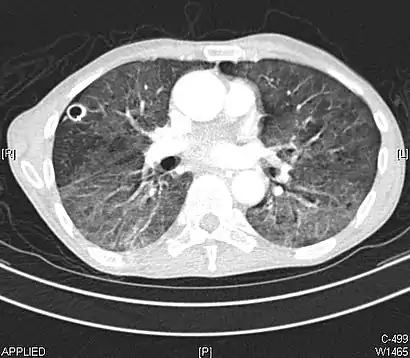

CT image showing ground-glass nodule (circled).